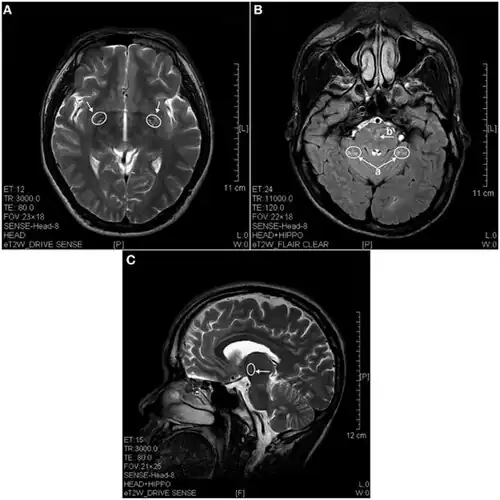

In 2013 a study using magnetic resonance imaging showed brain lesions in ketamine addicts (using from 0.2g twice a week up to 1g daily for 0.5 up to 12 years) with severity depending on the duration of addiction and daily intake of ketamine. Cortical atrophy and holes in superficial white matter are seen early on. After 4 years of addiction lesions spread throughout the brain and damage is evident in the pons and other deeper brain structures.[17]